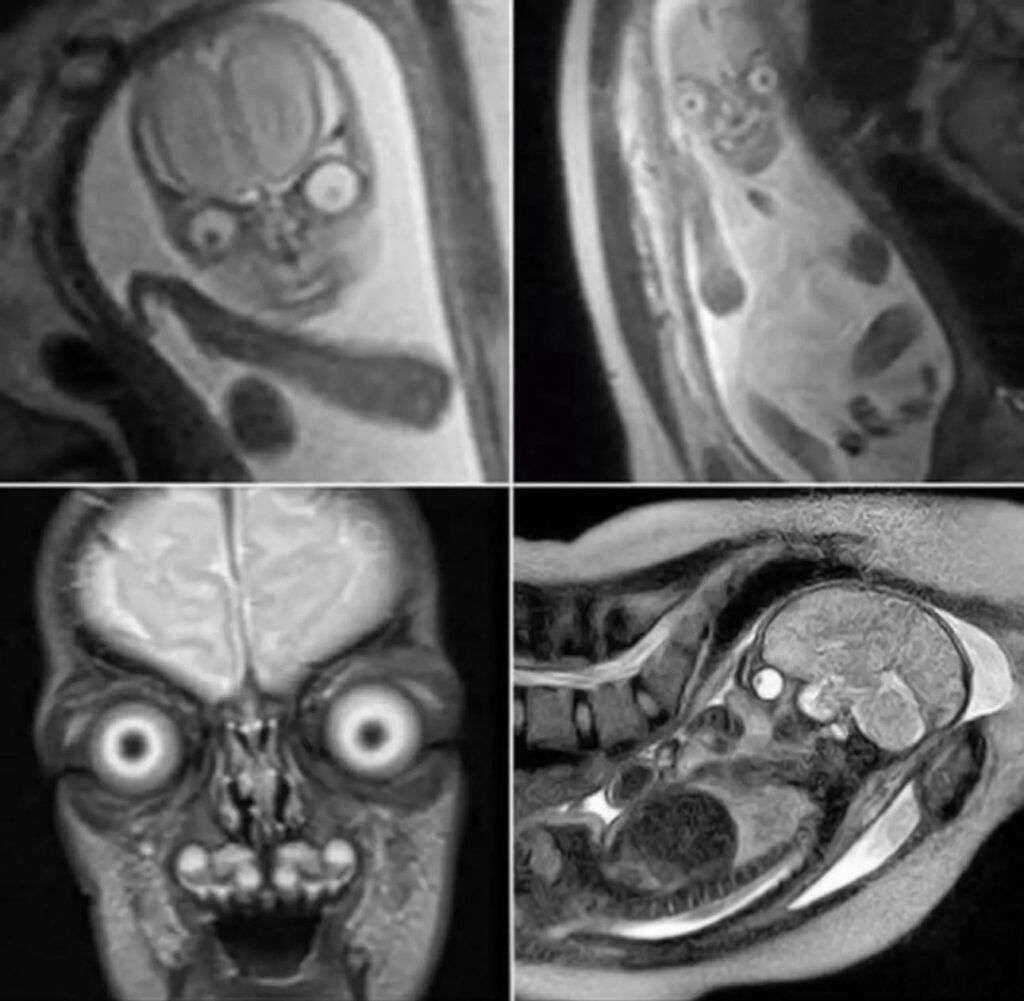

Aunque la resonancia magnética (RM) no representa un peligro inmediato, no se utiliza como estudio de rutina en embarazos normales. Su uso se reserva para casos puntuales, especialmente cuando el ultrasonido no proporciona información suficiente o se requiere un análisis más detallado de los tejidos blandos o posibles anomalías.

La RM es particularmente valiosa cuando se necesita una evaluación precisa del sistema nervioso central del feto, problemas en órganos internos o alteraciones estructurales que no son visibles con claridad mediante ultrasonido. Sin embargo, debido a su alto costo, mayor duración y requerimientos técnicos, no se justifica emplearla en todos los embarazos.